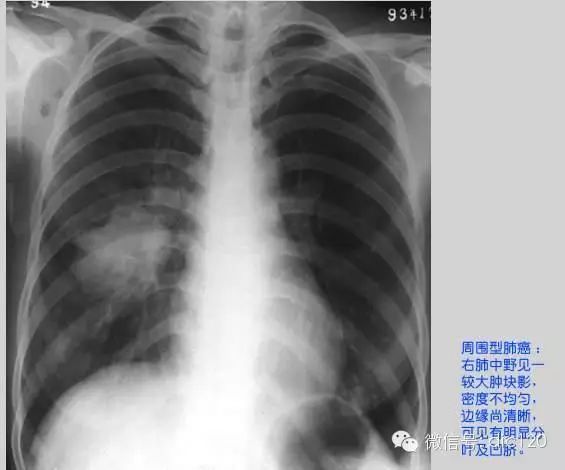

②分葉征(lobulation)

,是指腫塊的輪廓並非純粹的圓形或橢圓形,表麵常呈凹凸不平的多個弧形,形似多個結節融合而成,通常可分為深分葉和淺分葉,以分葉部分的弧度為標準:弦距與距長之比>2/5為深分葉。病理基礎一是與腫瘤邊緣各部位腫瘤細胞分化程度不一,生長速度不同有關。二是肺的結締組織間隔,進入腫瘤的血管、支氣管分支、從腫瘤內向外生長的血管和結締組織等可引起腫瘤生長受限,產生凹陷,從而形成分葉的形態。深分葉征在肺癌診斷中有重要意義。技術上以靶掃描為佳,重疊重建常有必要,結合橫斷麵和非橫斷二維圖像可以有效區分,3D重建則可提供直觀但並不很精確的圖像。